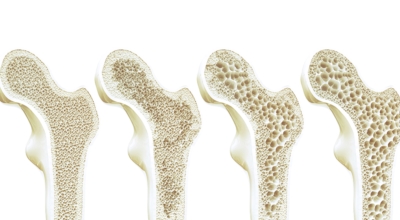

콩에는 칼슘과 이소플라본이라 하는 단백질 물질이 다양하게 포함되어 있는데요 이소플라본 물질이 뼈를 만들어 주는 세포를 강화시켜서 골밀도를 높여주며 뼈에서 칼슘이 빠져나가게 하는 파골세포 활성을 억제하는 효과가 있습니다 그리고 여성호르몬인 에스트로겐과 비슷한 역할을 하기 때문에 갱년기의 여성들에게는 좋은 음식이라고 볼 수 있어요.

또한 콩에 함유되어있는 칼슘은 뼈에 흡수가 잘 되기 때문에 골다공증 예방에 좋습니다 두부는 콩보다 칼슘을 빨리 흡수한는 것으로 알려져 있다고 하며 뼈가 약해지지 않도록 골밀도를 높여주는데 큰 장점이 있답니다.